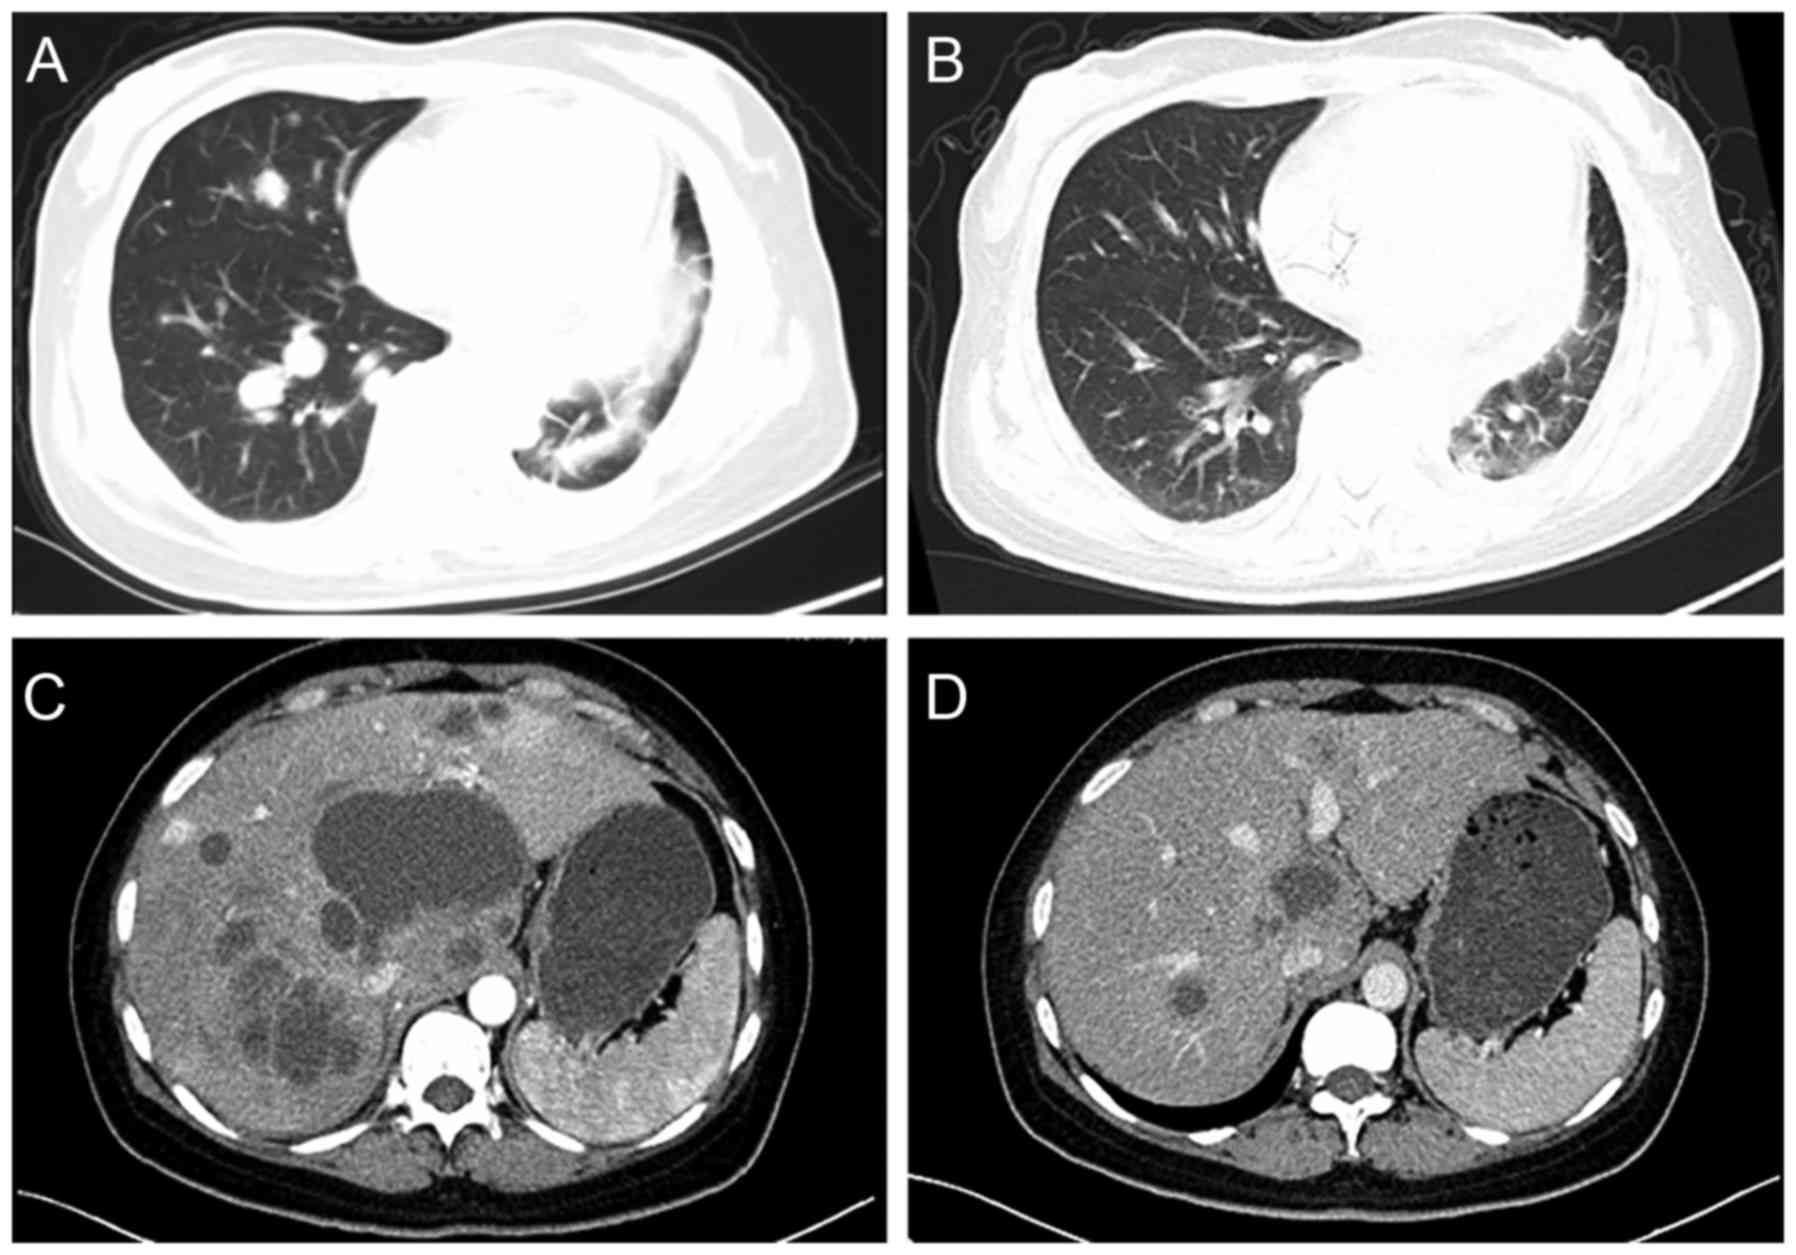

In the chemotherapy-bevacizumab group, 9 patients achieved a PR, of which 3 were squamous cell or adenosquamous carcinoma, and 16 exhibited SD, of which 1 was adenosquamous carcinoma. In the chemotherapy-alone group, 2 patients achieved a PR and 10 exhibited SD. There was a significant improvement in ORR and DCR for the chemotherapy-bevacizumab group compared with the chemotherapy-alone group (ORR, 23.7 vs. 5.3%, respectively, P<0.001; DCR, 65.8 vs. 31.6%, respectively, P<0.001). Computed tomography scans of 2 patients with PR are shown in Fig. 1. Of these patients, 1 patient was a 51-year-old female with stage IV adenocarcinoma, who received gemcitabine plus bevacizumab as a fourth-line therapy. This patient received a total of 6 cycles of treatment, and following 2 cycles of treatment, there was a marked reduction in size of the pulmonary lesions. The PFS of the patient was 3.9 months, but she succumbed subsequent to follow-up for 9.1 months. The other patient was a 42-year-old female with stage IV squamous cell carcinoma, who received gemcitabine plus bevacizumab as a fifth-line therapy, and primarily targeted lesions in the liver. The hepatic lesions were notably reduced in size following 2 cycles of treatment. This patient exhibited a total of 10 months for PFS and survived until the cut-off point.

Figure 1.

Examples of response to treatment with chemotherapy plus bevacizumab. CT images of a 51-year-old female with stage IV adenocarcinoma following (A) pre-treatment with chemotherapy-bevacizumab on 1st December, 2012 and (B) post-treatment with chemotherapy-bevacizumab on 6th February, 2013. CT images of a 42-year-old female with stage IV squamous cell carcinoma following (C) pre-treatment with chemotherapy plus bevacizumab on 9th May, 2015 and (D) post-treatment with chemotherapy-bevacizumab on 10th July, 2015. Images A and C were captured at baseline. Images B and D were captured following 2 cycles of chemotherapy-bevacizumab.